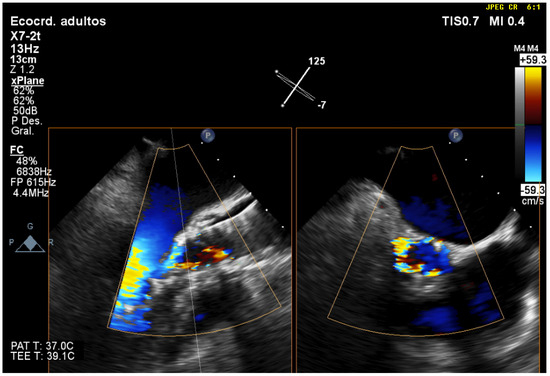

| 3 | Three-dimensional TEE is the best technique to detect and quantify perivalvular regurgitation after TAVR implantation, a fundamental aspect in deciding whether immediate valve postdilation is needed or not. |

| 5 | Three-dimensional TEE allows us to accurately evaluate cardiac function after TAVR, with important aspects such as systolic function or mitral valve function, which can be affected by TAVR when the implant is low, or due to damage caused to the subvalvular apparatus by the catheters and guides. |